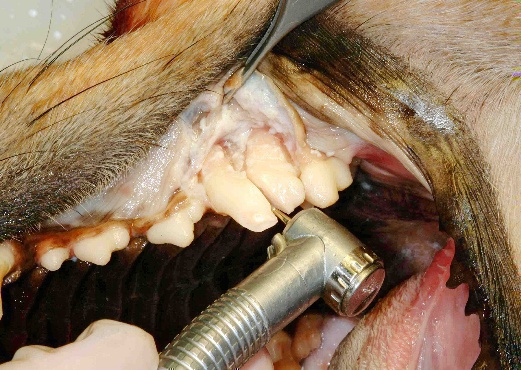

Sectioning the distal crown-root segment from the mesial segments for 208 in a canine cadaver